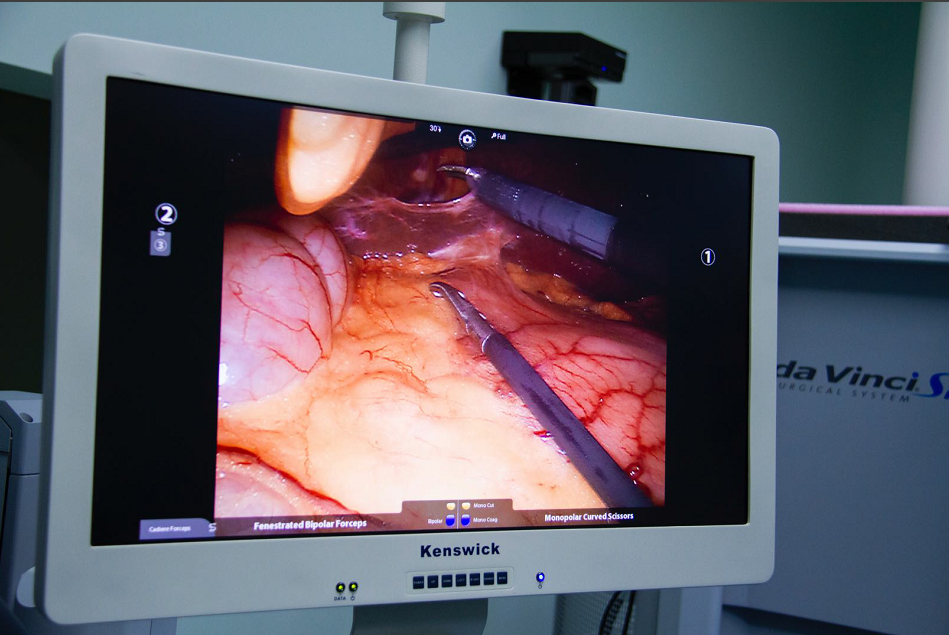

达芬奇手术机器人是目前全球较为先进、应用广泛的内窥镜系统,代表着当今手术机器人最高水平。截止2018年6月底,全球累计安装达芬奇系统4528台,其中美国有3010台。自2006年国内引进首台达芬奇手术系统以来,已有70多台达芬奇手术系统投入临床使用,全国TOP50的顶级医院均配备了达芬奇手术系统,截止2018年10月,全国达芬奇手术已经突破十万例,让十万名患者享受到了达芬奇先进微创技术的益处。

达芬奇手术机器人给患者手术中

达芬奇手术机器人的全称是内窥镜手术器械控制系统(英文名da Vnici S),它与腹腔镜系统相结合,主刀外科医师在远离手术台的操作控制台,用手遥控着装配在手术台上的4个机械臂,控制连接在机械臂上的腹腔镜和手术器械的动作和运转,完成各类手术。可以说达芬奇手术机器人的出现,将外科医师从手术台上解放了出来。

1、机器人的摄像系统为外科医师提供了更清晰和逼真的三维视野,机器人的“眼睛”高清立体,手术视野放大10倍,细小的组织也难逃火眼金睛;

光学放大10倍的高清晰立体图像